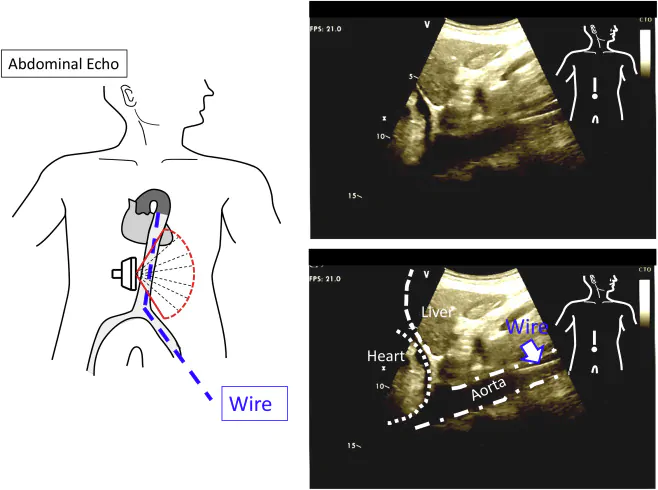

Проводник и устройство, похожее на баллон (катетер), вводят в аорту через бедренную артерию, и надувают баллон, который блокирует аорту, уменьшая приток крови к месту травмы, но поддерживая его к жизненно важным органам, таким как сердце и мозг. Ультразвуковое исследование на месте (POCUS) можно использовать для контроля и проверки положения проводника и баллона во время процедуры. УЗИ используется для выявления общей бедренной артерии над ветвью глубокой бедренной артерии и визуализации прохождения иглы в общую бедренную артерию.

Техника УЗИ брюшной полости для процедуры REBOA

- Установите датчик в середине верхней части живота и сканируйте аксиальное изображение 2-й зоны брюшной аорты, которая обычно расположена перед поясничным позвонком.

- Прижмите датчик по направлению к брюшной стенке, в случае если не сканируется четкое изображение (через газ в желудке или поперечно ободочной кишке). При нажатии на датчик газ под датчиком освобождается и сканируется четкое изображение. Если проводник находится во 2-й зоне брюшной аорты, проводник также сканируется.

- После сканирования аксиального изображения брюшной аорты датчик поворачивается на 90° по часовой стрелке и сканируется сагиттальное изображение.